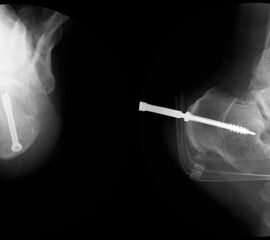

Bei Rückfussfehlstellungen ist meist eine knöcherne Korrektur des Kalkaneus indiziert. Dabei wird das Fersenbein im Bereich des Tuber calcanei durchtrennt und der Achillessehnenansatz nach medial oder lateral geschoben. Zusätzlich ist eine Rotation des Tuber möglich, wodurch sich der Korrektureffekt noch verstärkt. Durch die Wahl der Osteotomieebene kann die Verscheibung mit einer Verlängerung oder Verkürzung des Fersenbeins kombiniert werden. Die Osteosynthese erfolgt typischerweise durch perkutan eingebrachte Schrauben.

Operationsplanung anhand der Röntgenaufnahmen unter Beachtung wichtiger radiologischer Landmarks wie Rückfussachse, Metatarsale I – Talushals-Achse im dp und lateralen Strahlengang (Abbildung 1 und 2).

Kanülierte Schrauben bis 80 mm Länge.

Kirschnerdraht mit 2,0 mm zur Verschiebung des Tuber calcanei.